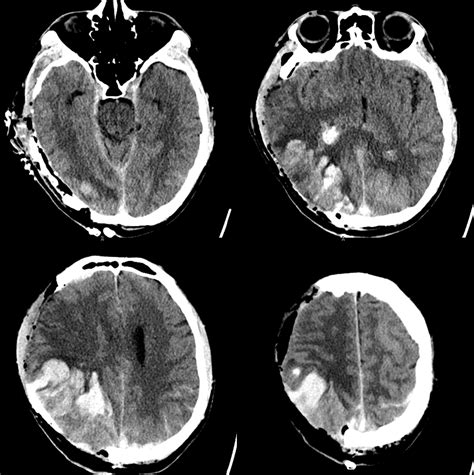

Traumatic injury to the SSSV can occur in cases of head trauma, such as motor vehicle accidents or falls. Injury to the SSSV can lead to epidural hematoma, subdural hematoma, or intracranial hemorrhage. Symptoms may include headache, vomiting, and loss of consciousness. Diagnosis typically involves computed tomography (CT) or magnetic resonance imaging (MRI). Treatment may include surgical evacuation of the hematoma or intracranial pressure monitoring.

CTV is another non-invasive imaging technique that uses computed tomography (CT) to visualize the venous sinuses. It involves the injection of a contrast agent to enhance the visibility of the venous sinuses. CTV can detect abnormalities such as thrombosis, aneurysms, or tumors and is particularly useful in patients with suspected CVST or traumatic injury to the SSSV.